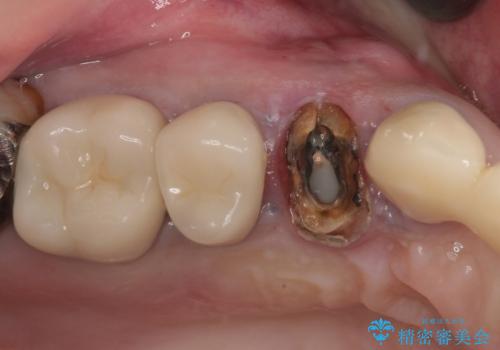

右下大臼歯 インプラント2本埋入後、フルジルコニアクラウンにて補綴

右上大臼歯 骨整形術後、フルジルコニアクラウンにて補綴